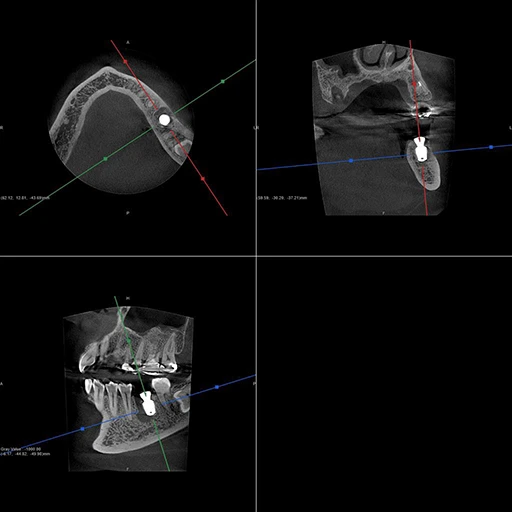

40代、女性、左下噛むと痛いこと主訴に来院され、インプラント治療を行いました。

| 診断結果 | 左下6番歯根破折 |

| 治療内容 | 抜歯即時インプラント |